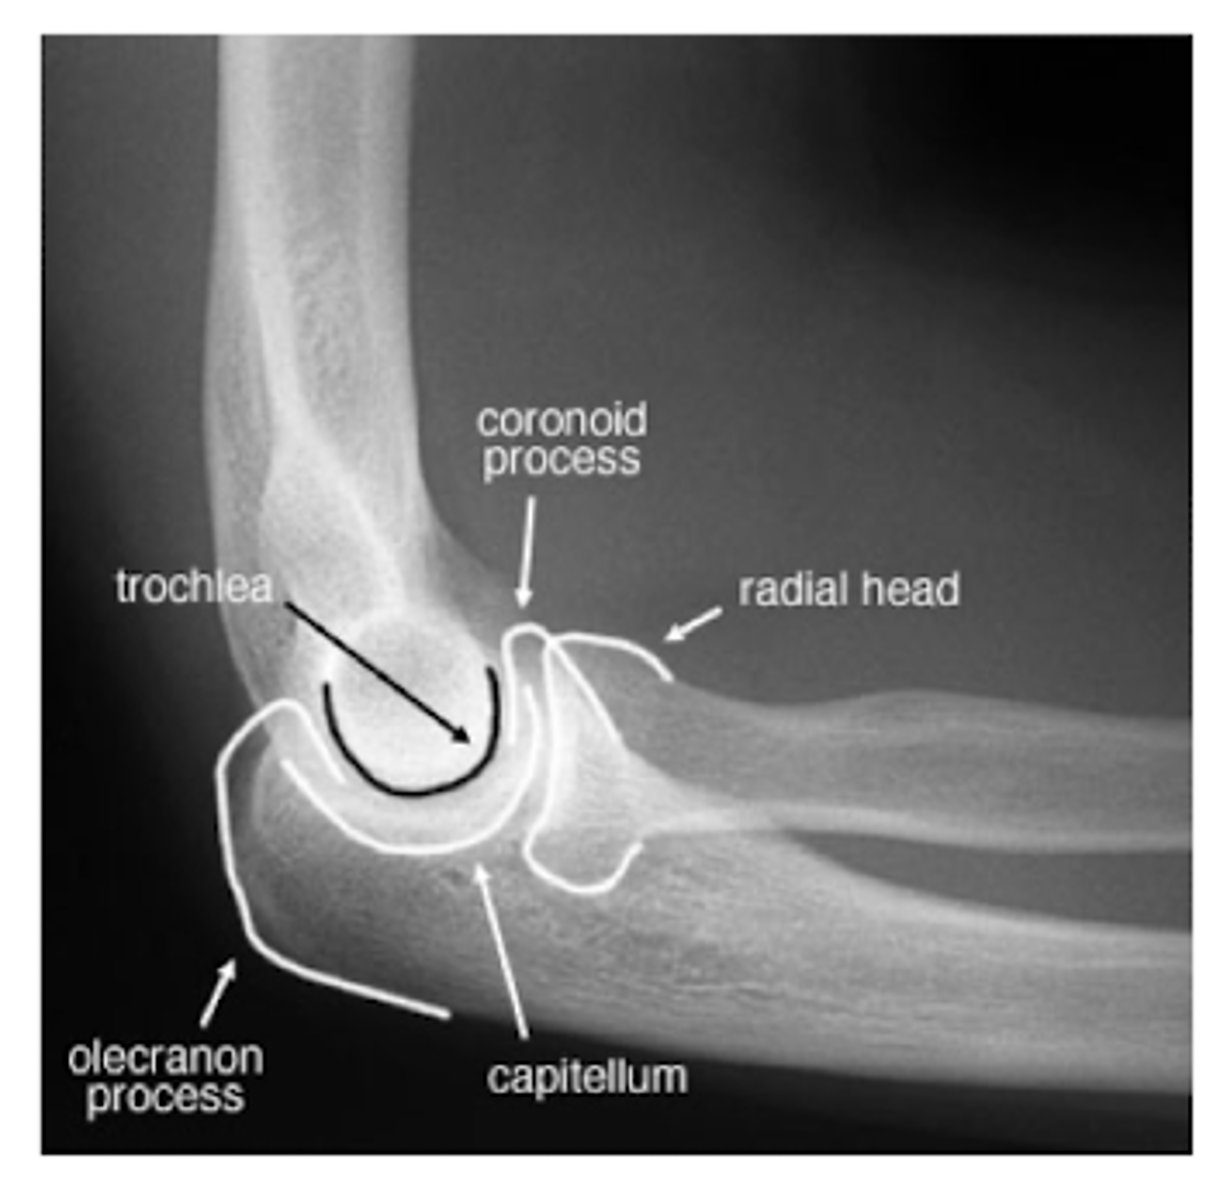

REVIEW: XR of elbow #2 (lateral view)

What does a fat pad sign/sail sign on elbow XR suggest? What type most common in adults and children?

presence an articular hemorrhage due to an occult or intra-articular fracture

Adults → radial head Fx

Children → supracondylar Fx of humerus